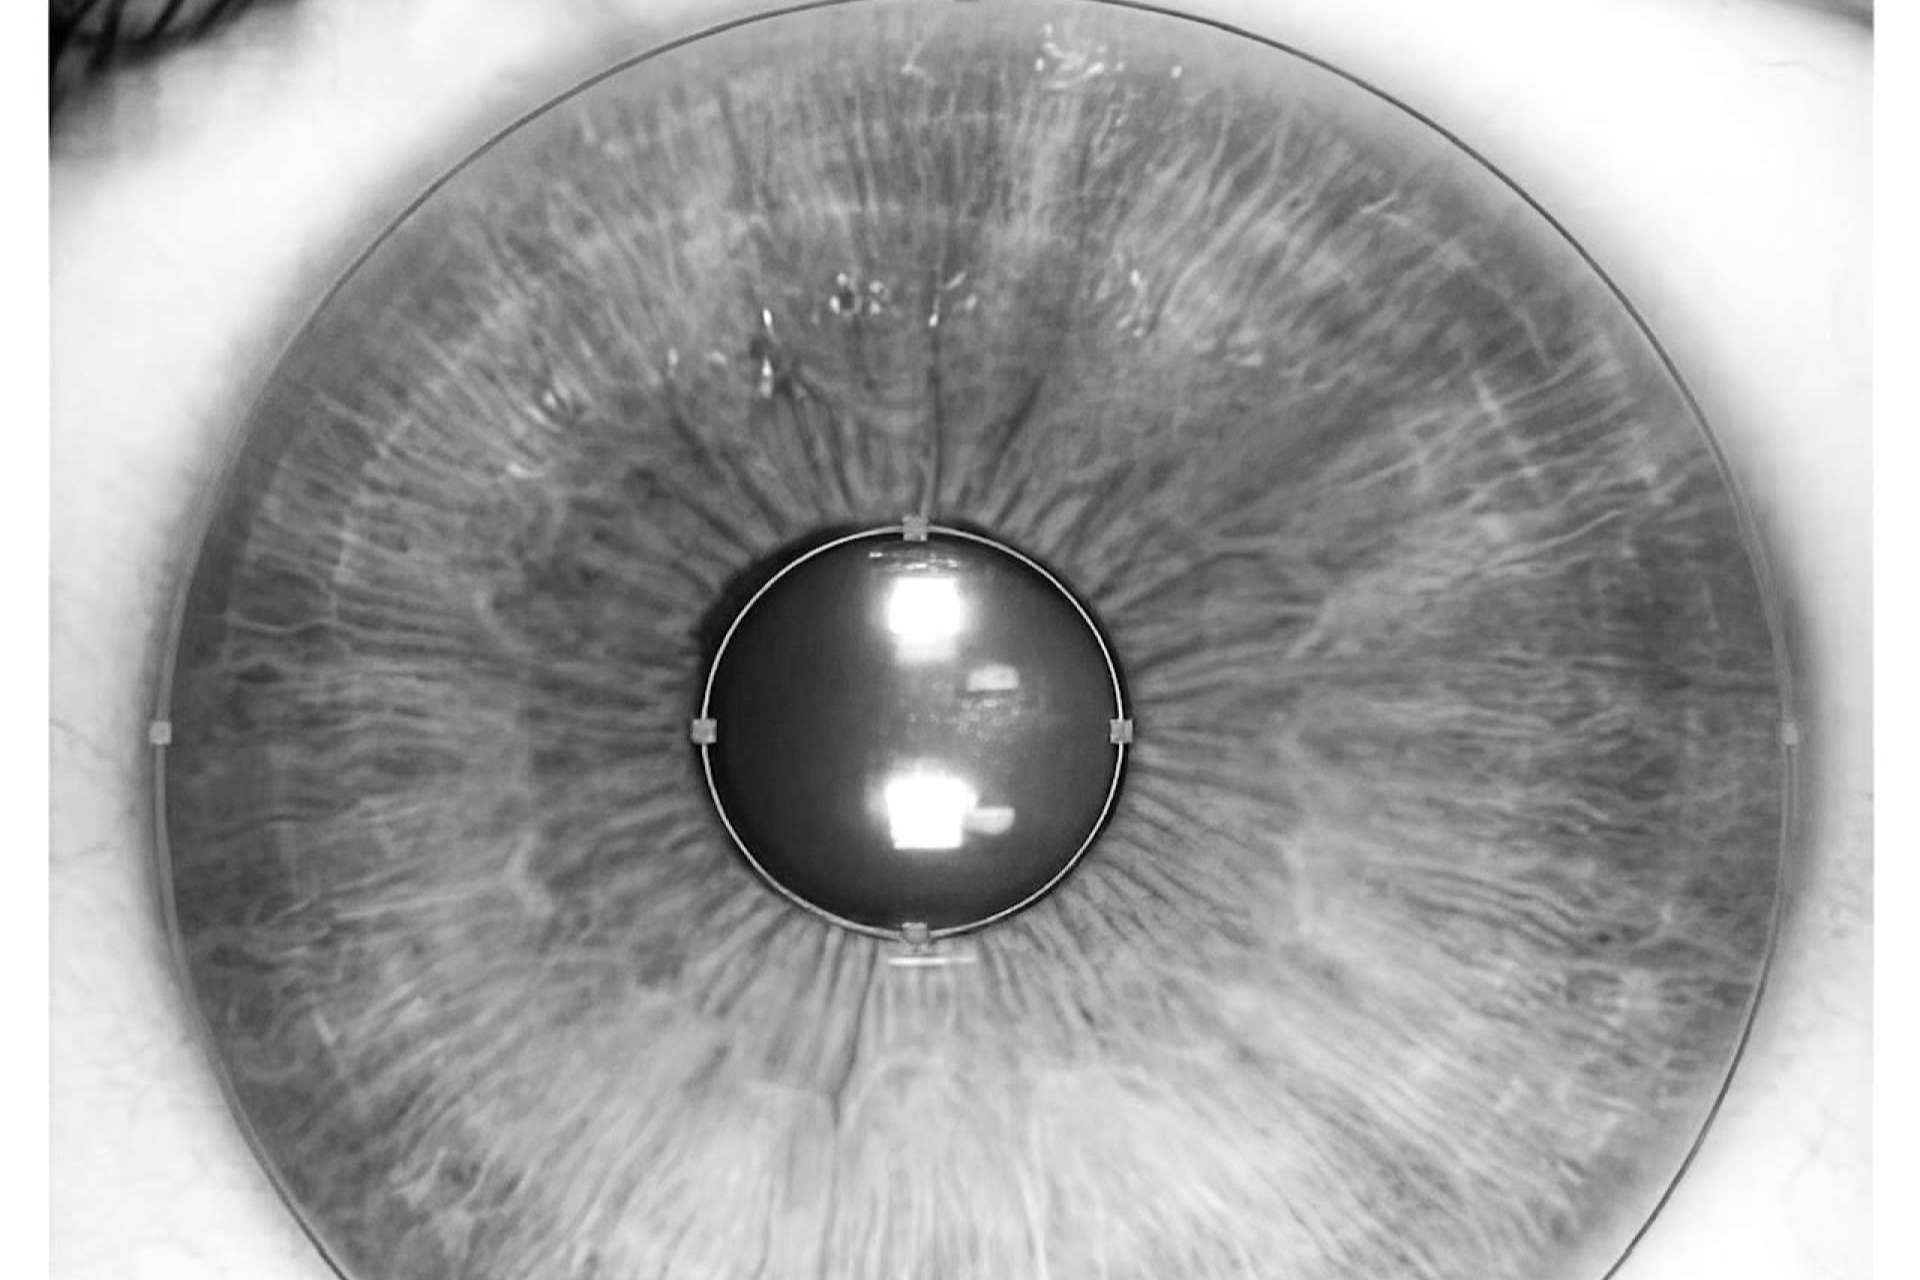

Un ejemplo de ello es el nuevo láser para cambiar color de ojos creado por los expertos oftalmólogos de Clínica Eyecos, llamado NewEyes 7G Ultimate Custom Laser, un dispositivo equipado con la más avanzada tecnología, que lo convierte en un óptimo láser para cambiar el color de los ojos de manera segura y predecible.

Lo último en tecnología láser para cambiar el color de ojos: NewEyes 7G Ultimate Custom Laser

La tecnología de NewEyes 7G Ultimate Custom Laser se ha consolidado a día de hoy como una de las técnicas más avanzadas para cambiar el color del iris de una manera eficaz, segura y predecible. Sus resultados son extraordinariamente naturales, y lo mejor es que prácticamente no genera ningún contratiempo para el paciente, careciendo de las complicaciones clínicas generalmente asociadas a las intervenciones oculares. Además, NewEyes 7G Ultimate Custom Laser es un óptimo láser para cambiar el color de ojos, porque permite que el procedimiento se haga de manera ambulatoria y no quirúrgica, de forma más rápida, cómoda y segura para el paciente. Por otro lado, también hay que destacar que la tecnología NewEyes 7G Ultimate Custom Laser de Clínica Eyecos cuenta con una tasa de eficacia muy alta, logrando eliminar de manera satisfactoria el pigmento melánico de la cara anterior del iris en casi el 100 % de los casos, consiguiendo resultados extraordinarios.

Cuando se habla del cambio de color de los ojos mediante láser, muchas personas tienden a cuestionarse si el proceso realmente no conlleva riesgos. En el caso del NewEyes 7G Ultimate Custom Laser, su uso ha probado ser altamente seguro. De hecho, tras miles de intervenciones realizadas por la clínica, hasta el momento, no se han observado cambios refractivos, elevación de la presión intraocular o disminución de la agudeza visual una vez completado el tratamiento. Además, hay que destacar que para Clínica Eyecos la seguridad del paciente es una prioridad, por lo cual siempre se realiza una previa y rigurosa evaluación del paciente, para así determinar si puede o no ser un candidato para el tratamiento. Hacer esto es precisamente uno de los pasos más importantes, que ayuda a mantener una tasa de efectividad tan alta.